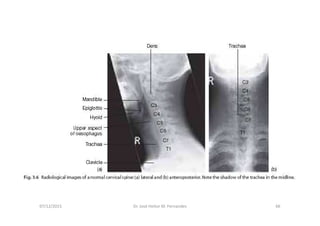

Anatomia Radiológica Cervical

1. Radiografia Simples

Radiografia da coluna cervical

http://www.info-radiologie.ch/radiografia-coluna-cervical.php

Série de Radiografias Simples

da Coluna Cervical

• 1- Incidência AP com a boca aberta (para visualizar C1-C2);

• 2- Incidência AP cervical inferior;

• 3- Incidência cervical lateral (perfil);

• 4- Incidências oblíquas direita e esquerda;

• 5- Incidências adicionais:

- Incidência lateral em flexão e extensão

- Incidência de Fuch

- Incidência dos pilares de Boyleston

07/12/2015 Dr. José Heitor M. Fernandes 65

AP Lateral

07/12/2015 Dr. José Heitor M. Fernandes 66